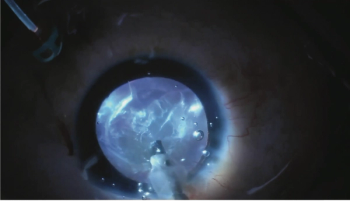

Zonular crises occur due to many different aetiologies, but ophthalmologists now have multiple tools available to solve complex problems and achieve excellent results in complex cases.

The companies note that data from Study CPN-302 confirm the results in the first Phase 3 study, CPN-301, and they demonstrate the clear benefits of treating patients after cataract surgery with APP13007.